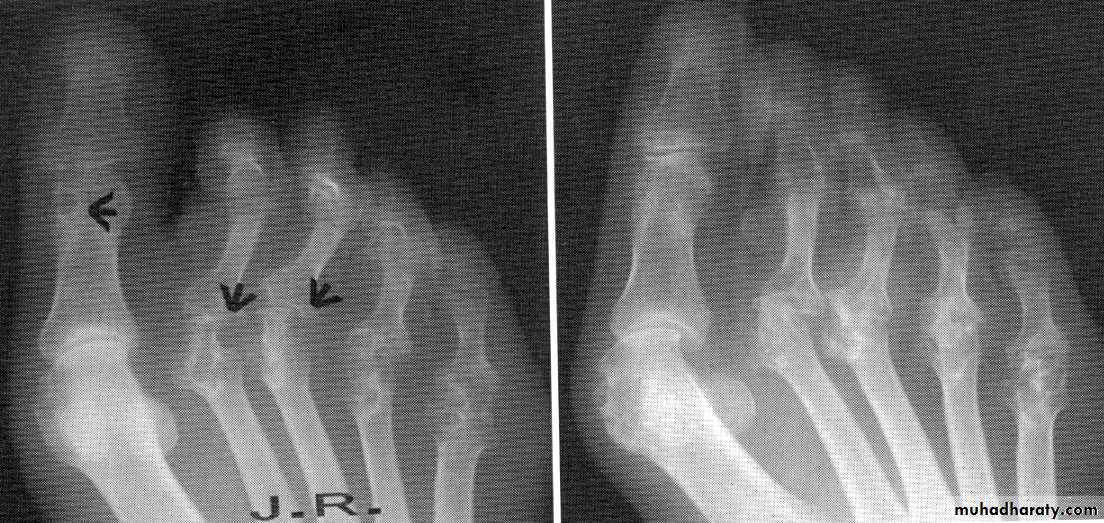

Tendon and bursa involvement are frequent and often clinically dominant in the early disease. RA can affect any joint, but has a predilection for metacarpophalangeal, proximal interphalangeal and metatarsophalangeal joints, as well as the wrists and knees.

dorsal subluxation of ulnar styloid of the wrist , trigger finger, cock up deformity of the toe, flatfoot, Baker's(popliteal) cyst which can be mistaken for DVT, but past history of joint disease & Doppler U/S can establish the diagnosis of DVT.

3- X-ray: the typical radiographic changes of RA are periarticular osteopenia& marginal non proliferative erosions.